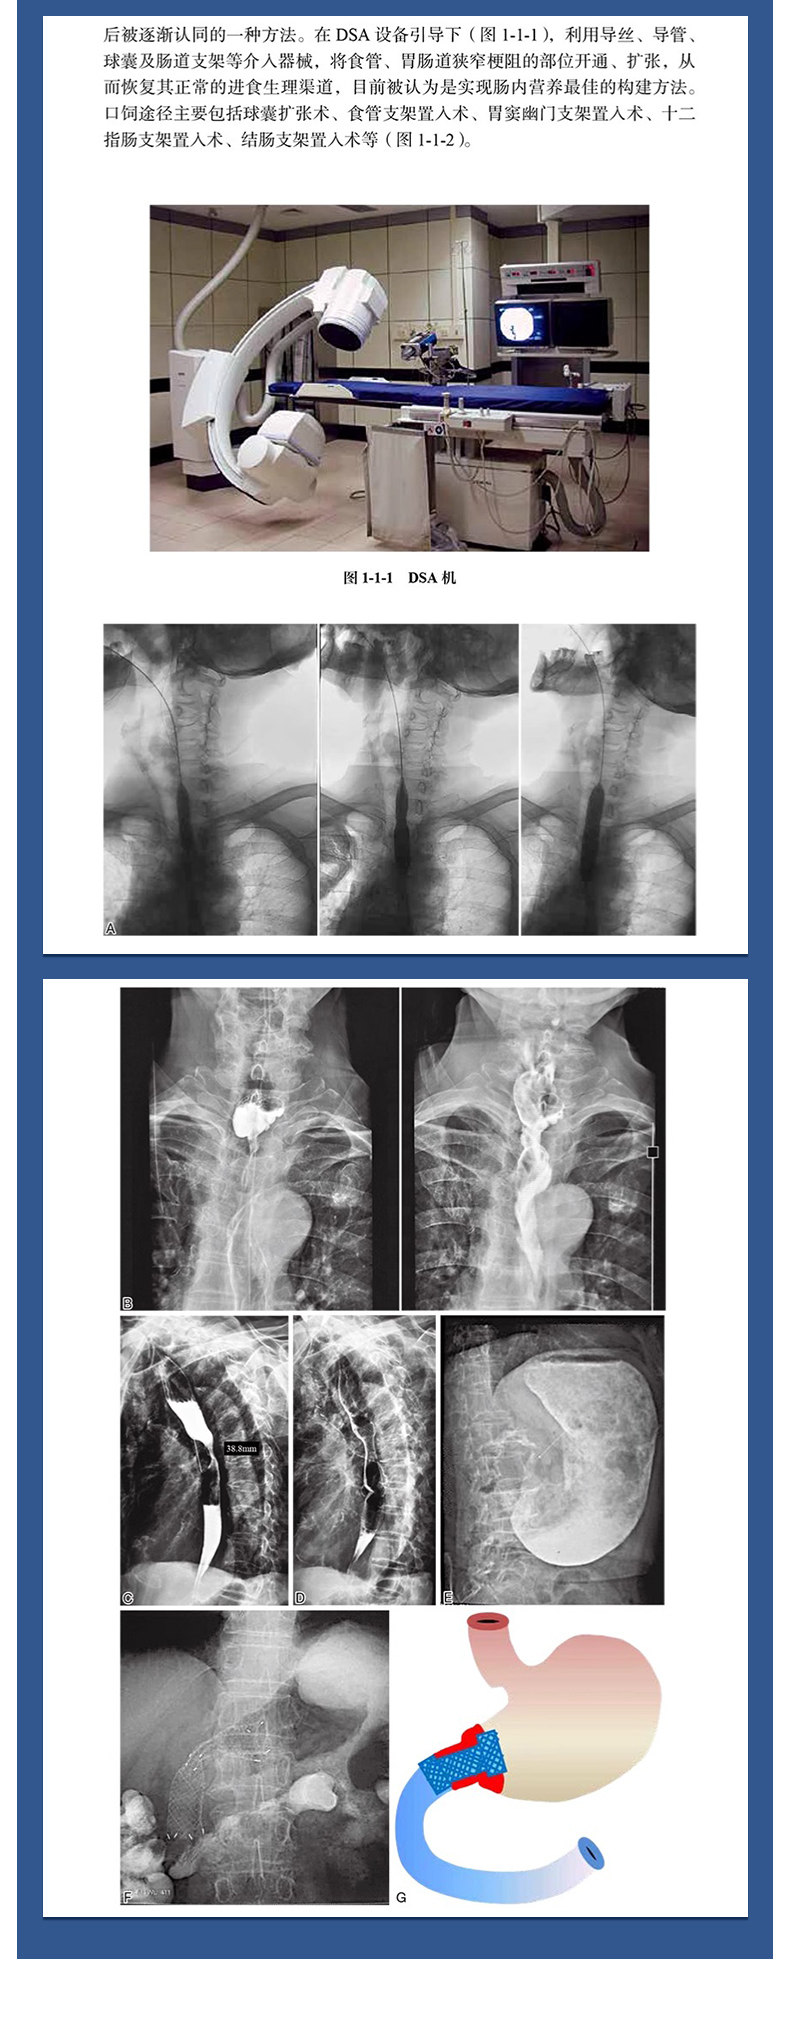

本书主要阐述以介入手段主导的肠内营养通路构建方法,主要包括"六大"肠内营养通路构建新技术:①鼻饲营养管置入术;②消化道支架置入术;③消化道狭窄球囊扩张术;④肠梗阻导管置入术;⑤X线引导下经皮胃造瘘术;⑥消化道造影检查技术等。这些新的肠内营养通路的构建技术为不能经口正常进食的患者提供了维持生命的营养快线,以其微创、快捷、经济福泽广大的患者。 本书共分4章19节,第一章主要介绍介入放射学与肠内营养治疗的发展现状、进展以及介入治疗技术在肠内营养通路建立中的应用,第二章介绍肠内营养通路构建所用的上述6个主要介入技术,第三章临床实践以多病例的形式阐明介入技术在肠内营养通路构建的应用,第四章介绍肠内营养通路构建术中护理及长期护理。